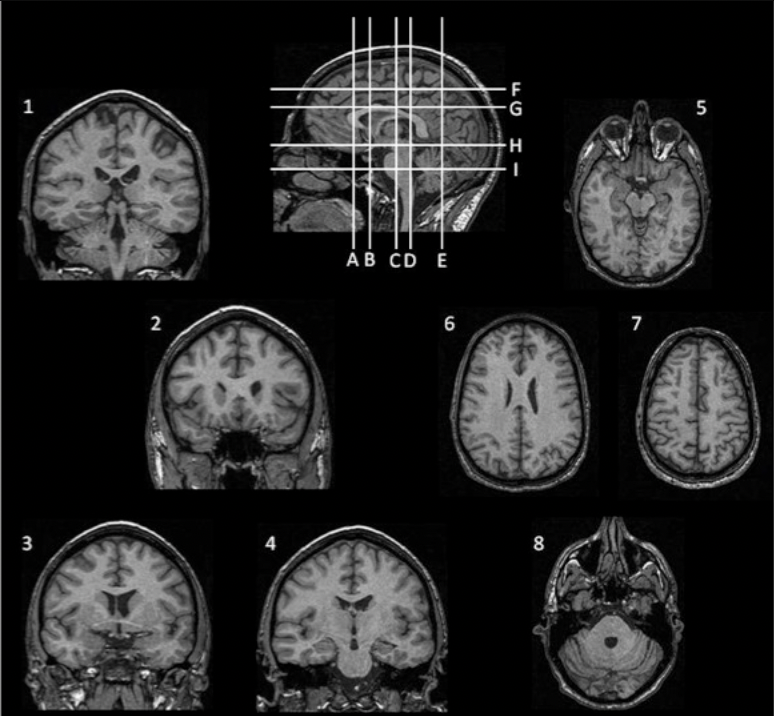

For the next two questions, match the images numbered 1-8 with the lines labeled A-I, which indicate possible locations of the sections through the head.

Identify the INCORRECT matching of image to section level.

A. image 6 = level G

B. image 3 = level B

C. image 1 = level D

D. image 8 = level E

E. image 5 = level H

Match the images numbered 1-8 with the lines labeled A-I, which indicate possible locations of the sections through the head.

Identify the CORRECT matching of image to section level.

[Note: the previous question asked for the incorrect match; this question is asking for the CORRECT match.]

A. image 6 = level F

B. image 4 = level I

C. image 2 = level H

D. image 7 = level G

E. image 3 = level B